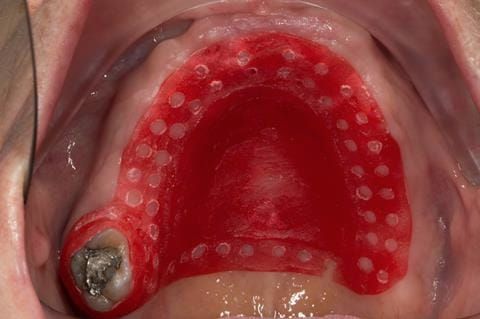

- Poorly fitting cobalt chromium based maxillary partial denture, which has been added to. This exhibited poor retention, stability and tissue fit (support). Unable to wear a new acrylic based denture.

- Cobalt chromium reinforced gasket denture - using a Molloplast B "O" ring to retain and stabilise the denture. This was my professional preference as this was the least invasive and simplest solution to this dental problem. Should the UR7 require removal in the future - an artificial tooth could be added - resulting in a complete denture. The patient would have adapted to the denture fully by this stage and have good neuromuscular control of the prosthesis.

Following consultation and second discussion appointment the patient chose to have option 2 namely, a window denture - maxillary cobalt chromium based partial denture. The clinical situation and treatment process is shown in detail below with photographs. The patient was successfully rehabilitated with this and her quality of life considerably improved. The clinical work was provided by Finlay and the technical work by Rowan.